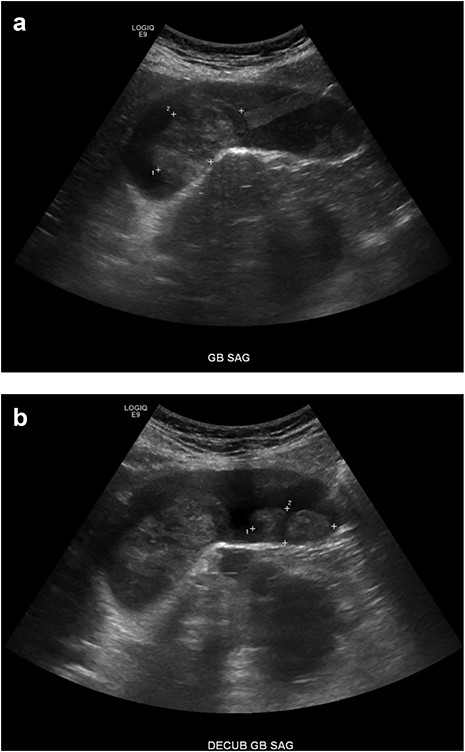

An 81-year-old male presented with the chief complaint of sharp right upper quadrant abdominal pain and nausea ongoing for 12 hours. The patient reported a similar, self-limited, episode 3 months previously. On presentation, leukocytosis 13 × 109/l, aspartate aminotransferase 83 U/l, alanine aminotransferase 49 U/l, lipase 78 U/l (normal 15–65), and total bilirubin 0.7 mg/dl. Abdomen and pelvis computed tomography (CT) demonstrated cholelithiasis in the gallbladder neck, soft tissue attenuation in the fundus of the gallbladder, mild extrahepatic biliary dilation and a common bile duct dilated to 10 mm (Fig. 1). Two well-circumscribed rounded filling defects within the gallbladder lumen, measuring 4.7 × 2.8 × 2.5 cm and 3.4 × 1.4 × 2.2 cm without distal shadowing, were visualized on right upper quadrant ultrasound (Fig. 2). CA 19-9 was negative (6.0 U/l). Magnetic resonance (MR) imaging was unable to be safely performed due to a metal prosthesis.

Right upper quadrant ultrasound. (A, B) A mildly distended gallbladder is visible containing two well-defined soft tissue masses within the gallbladder lumen, measuring 4.7 × 2.8 × 2.5 cm and 3.4 × 1.4 × 2.2 cm, respectively